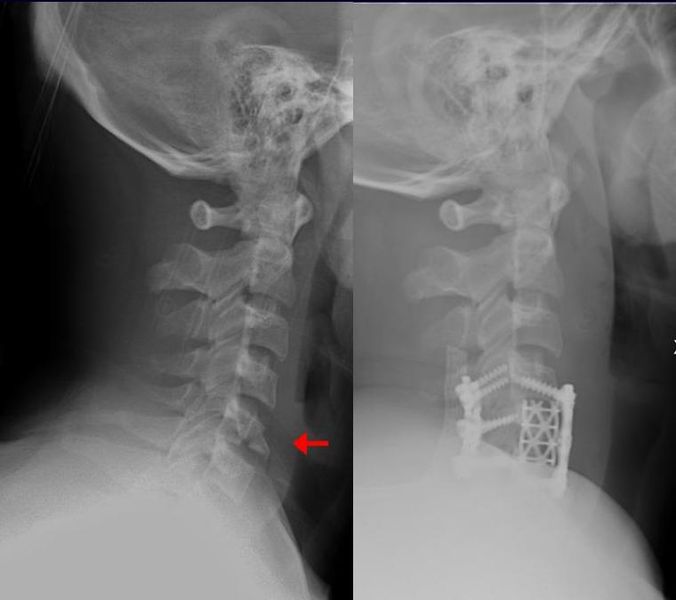

Anterior and lateral view x-rays of fractured left leg with internal fixation after surgery